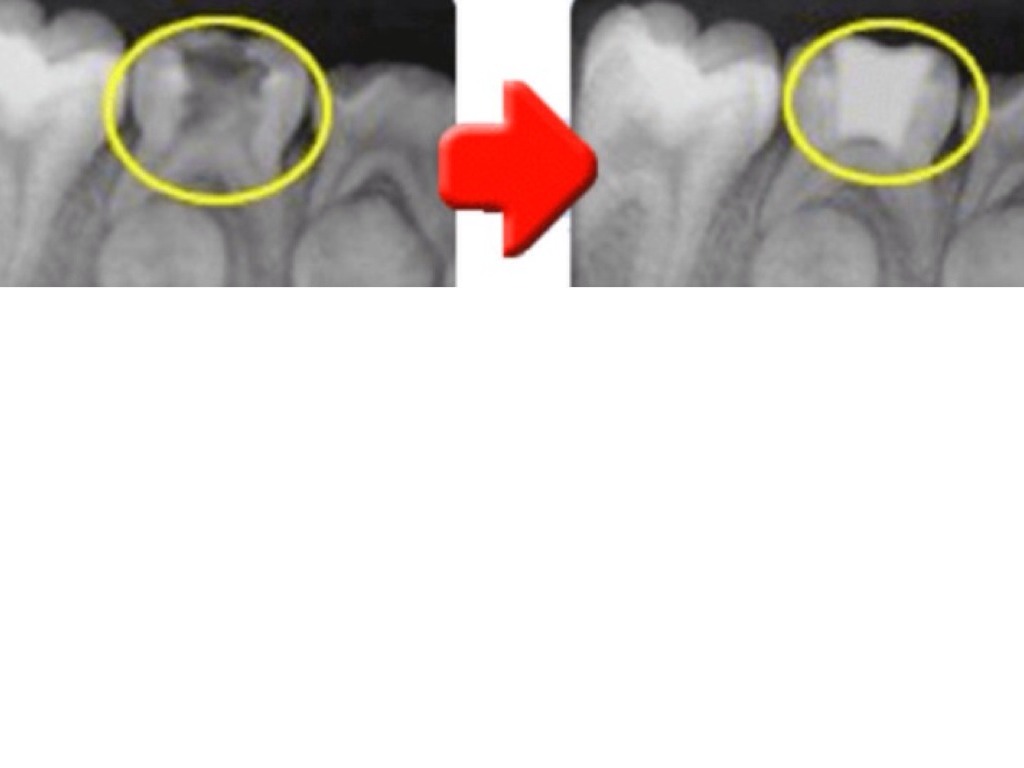

CARIES

Untitled Slide